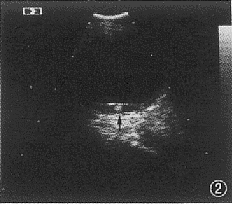

2 B超检查眼内囊尾蚴病 (活动期) , 视网膜下球形强回声光斑 (箭头) , 为头节影, 周围为无回声液性暗区, 其前方条状强回声光带为脱离的视网膜